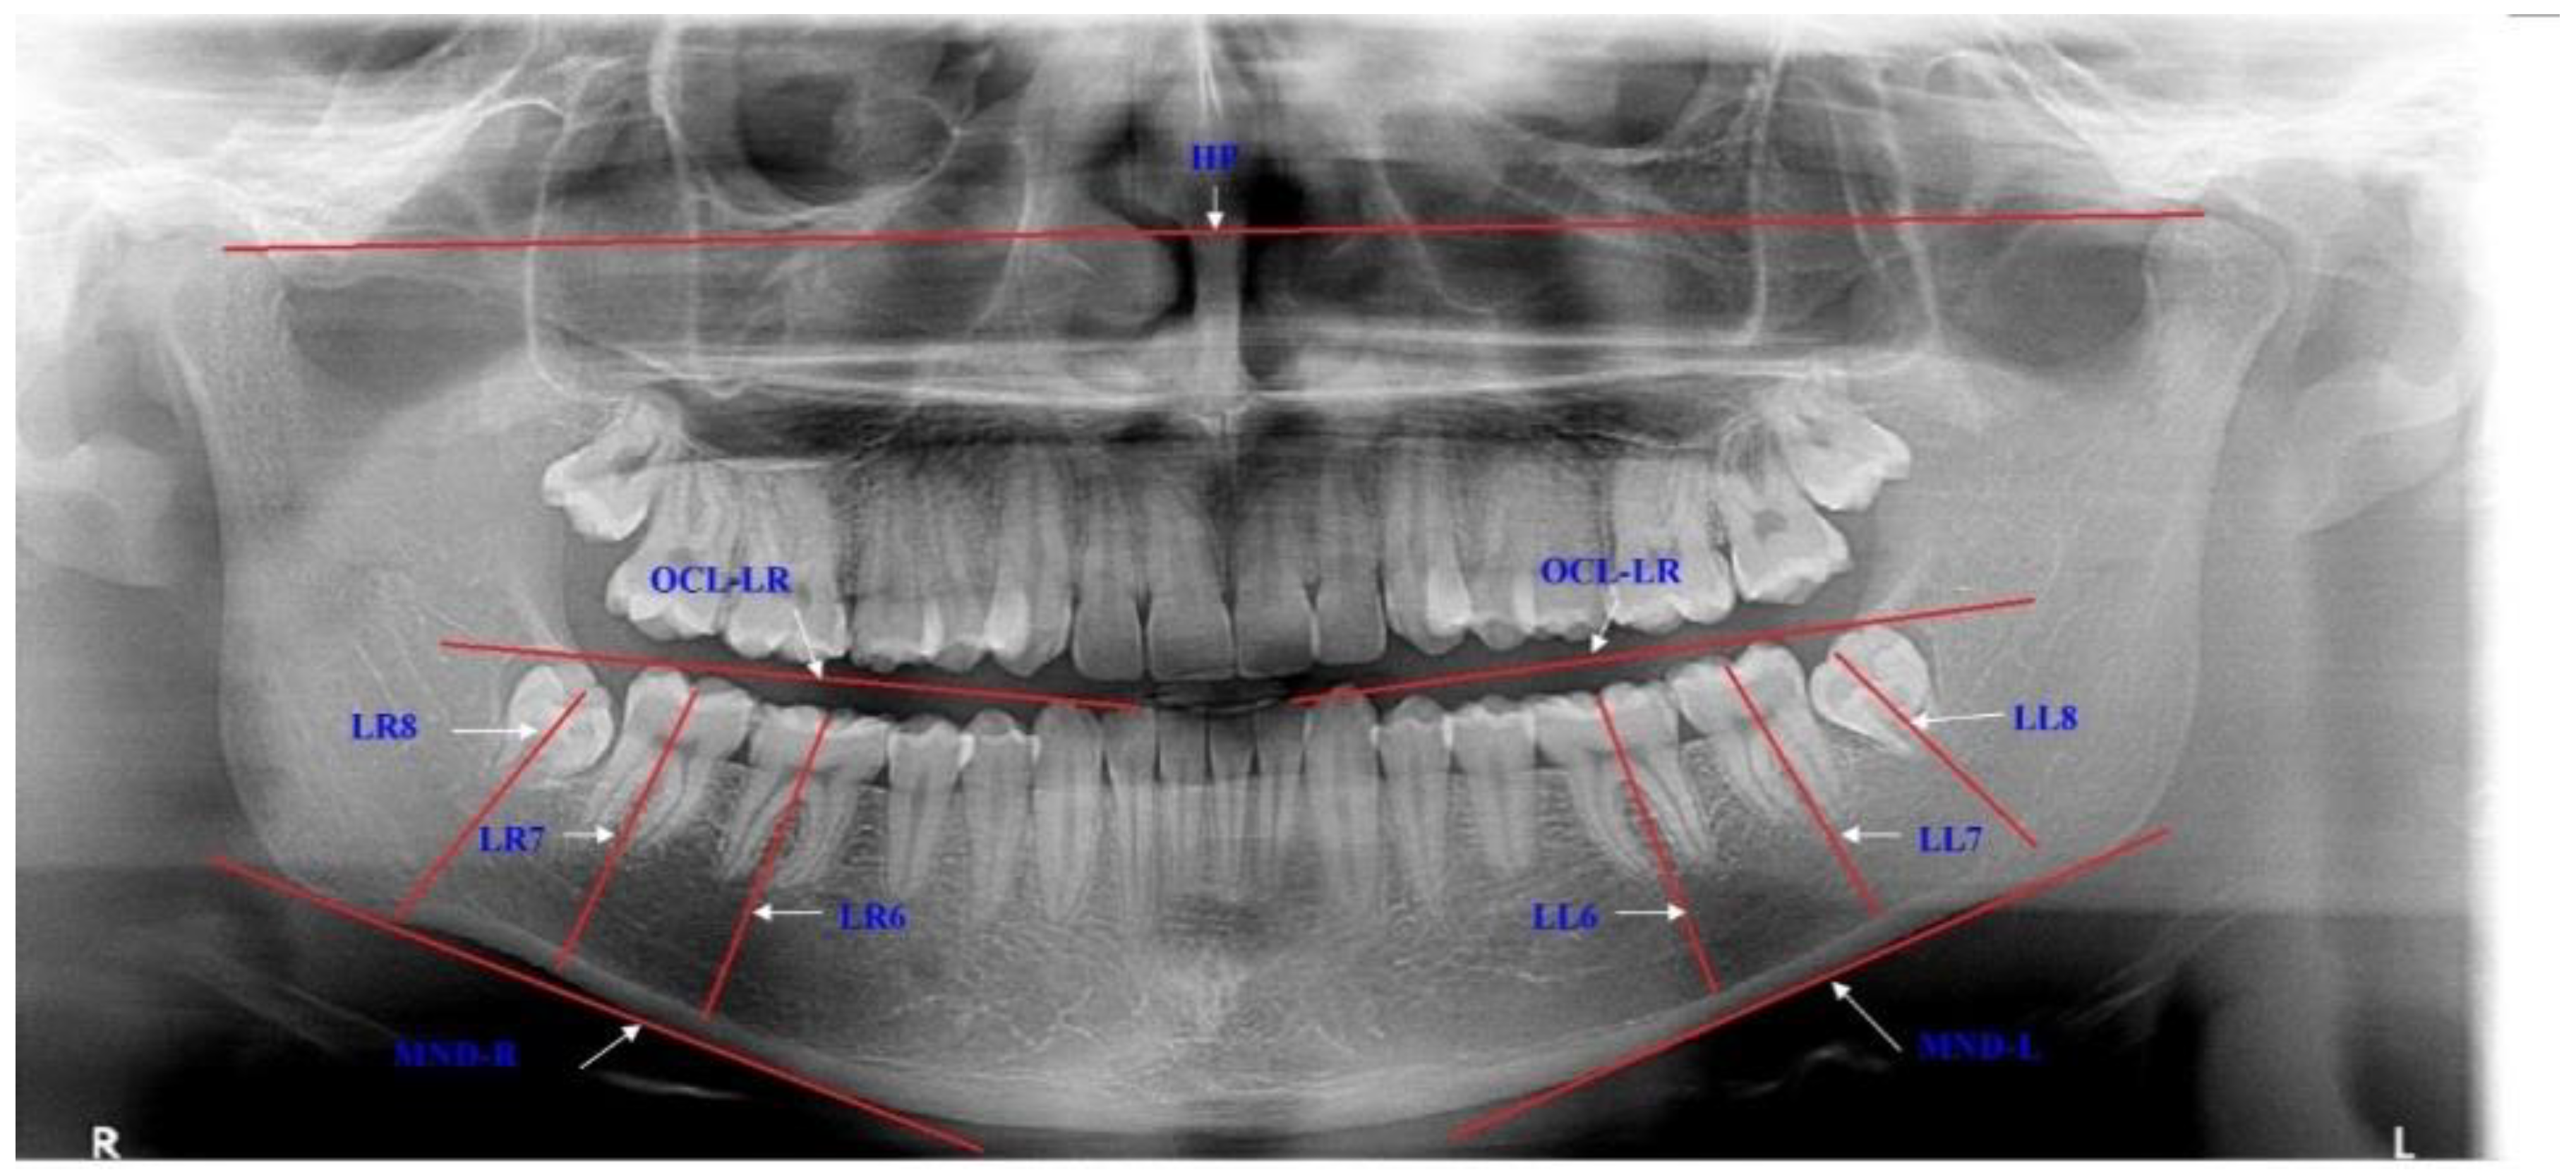

The impaction of the lower third molar was determined by the evaluation of each panoramic radiogram for the angulations and eruption levels of the lower molar and for the eruption space for the LM3. The positions of these teeth were determined using mandibular plane (MND), occlusal plane (OKL) and horizontal plane (HP) (Figure 1).

Figure 1.

Description of the variables for estimating the positions of the lower third molars. LR8—longitudinal axis of the lower right third molar is traced from the midocclusal point to the midpoint of the root bifurcation, and the same on the opposite side with LL8; LR7—longitudinal axis of the lower right second molar is traced from the midocclusal point to the midpoint of the root bifurcation, and the same with LL7; LR6—longitudinal axis of the lower right first molar is traced from the midocclusal point to the midpoint of the root bifurcation, and the same with LL6; MND-R—right mandibular plane is drawn through most inferior border of the mandible, and the same with MND-L; OCL-LR—lower right occlusal plane is drawn through the incisal edge of the lower right lateral incisor to the distal cusp of the lower right second molar, and the same with OCL-LL; HP—horizontal plane is traced through the most superior parts of the right and left condyles.